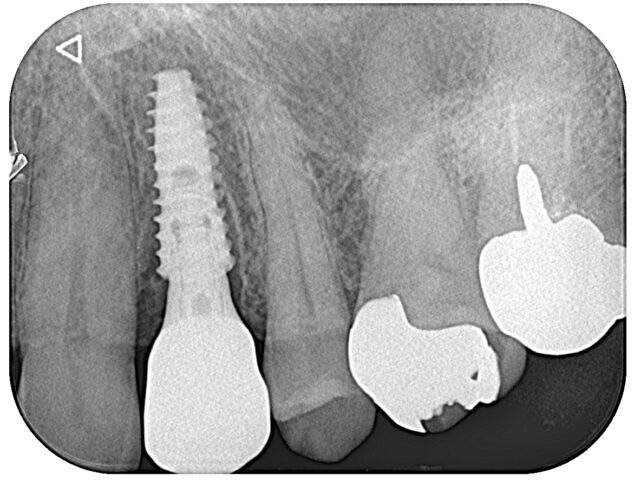

抜歯後即時埋入時 術後2週間後 補綴完成時

術後(パノラマ写真)

術前 術後